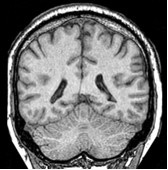

Une coupe mdio-sagittale de la fosse

postrieure montre lÕaspect grossirement triangulaire de la loge occupe par

le cervelet. Cet espace est dlimit par: le ple occipital en haut, le tronc

crbral en avant et lÕcaille occipitale en bas.

Imag. 01 - Coupe mdio-sagittale du crne (Atlas Sandoz)

Imag. 02 - Coupe mdio-sagittale de lÕencphale (CHU Rabat) |

Ces limits correspondent aux trois faces du

cervelet : une face antrieure ou ventrale (c) rattache au tronc crbral

(tc), et deux faces dorsales, dlimite par une crte, la face suprieure (a)

moule contre la tente dure-mrienne qui la spare du cerveau, et la face

infrieure (b) applique contre le squelette occipital.